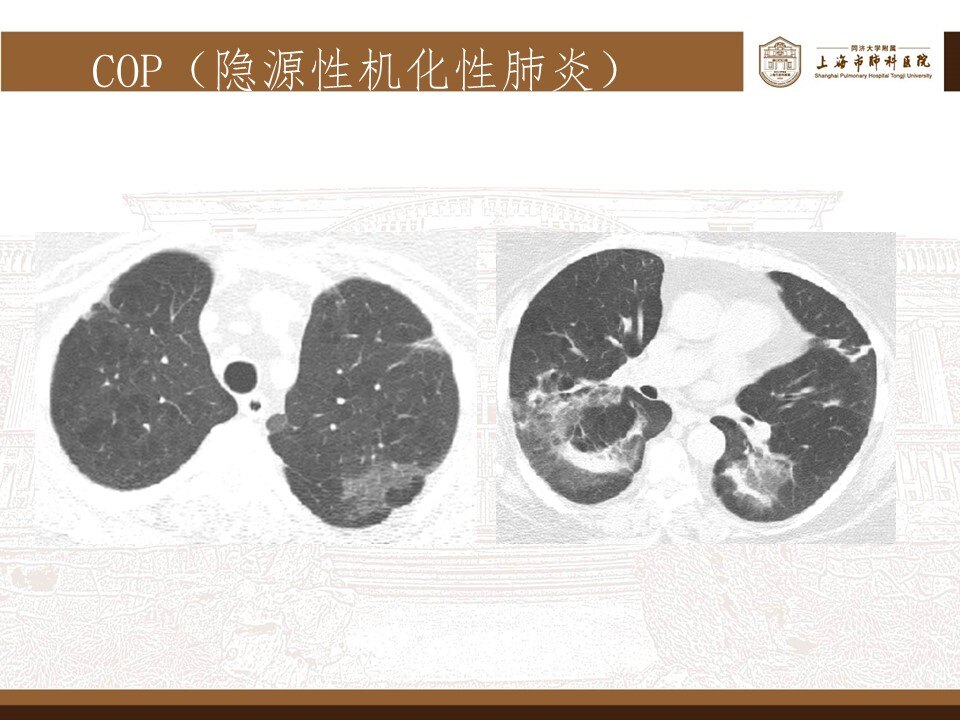

其实,这波omicron感染,确实肺炎比例比想象中要高,但很多都不会是大白肺,多数表现为双肺散发磨玻璃影,当然,也有单独的磨玻璃结节,特别容易表现为混合密度磨玻璃结节。其实很多新发的磨玻璃结节都是新冠肺炎,不用过于紧张,如果感染面积不大,一般临床上,也不需要特异性治疗,休息观察就行了。